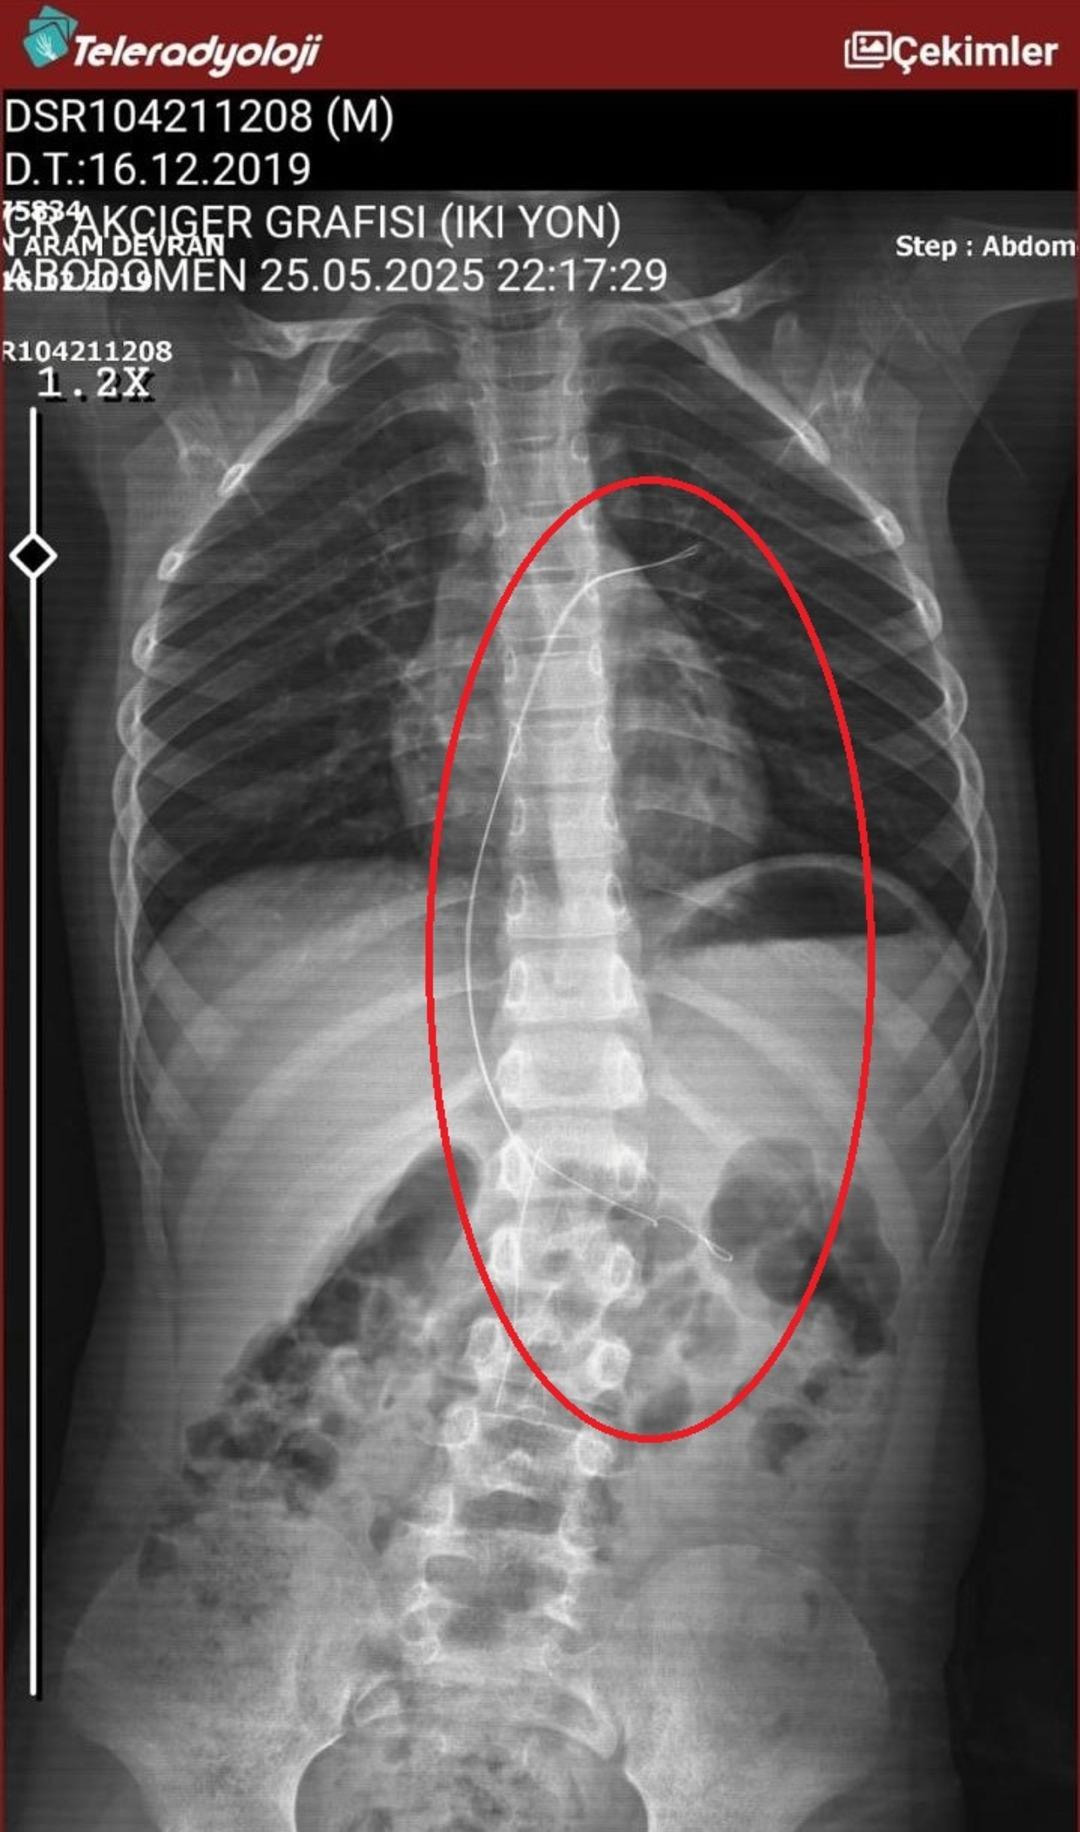

Seamore (37) ve Şaç'ta yaşayan Mehmet Ötün (40), Mayıs ayında bir parça salatalık yuttuktan sonra öksürük ve kusma şikayetleri gözlendiğinde Sernak Eyalet Hastanesine getirildi. Burada, ARAM gövdesinde yarıçap X ve manyetik rezonans görüntüleme unutuldu. Diyarbakir Gazi Yeşargil'in eğitim ve araştırma hastanesi jinekolojiye ve ARAM'lar için ek binaya yönlendirildi, 18 santimetrede 5.5 saatlik riskli cerrahi kaldırıldı. Postoperatif araştırmalarda, kateter kalp kapakına ve karaciğere zarar vermeye kararlıydı.

“Kateterin vücutta seyahat ettiği keşfedildi”

Aile avukatı Ahmet Yalçın, ikisinin de hastaneden şikayet ettiklerini ve bir dava açtıklarını açıkladı ve şunları söyledi: “Müvekkilim Eylül 2022'de Stevens -Johnson'un kariyeri nedeniyle Eylül 2022'de Dicole'deki üniversite hastanesinde tedavi edildi. Kateter ona saldırıya uğradı.